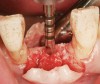

A round bur is usually used to mark the position where a 2-mm twist drill will be applied (Figure 1). Then the twist drill is employed to penetrate the cortical and trabecular bone (Figure 2). This provides information with respect to cortical bone thickness and medullary trabecular bone density. The amount of bone debris found on the twist drill can be interpreted as an indicator of bone quality (eg, the less debris and a more bloody appearance means softer bone). Four types of mineralized bone have been described by Misch (Table 1):1,2